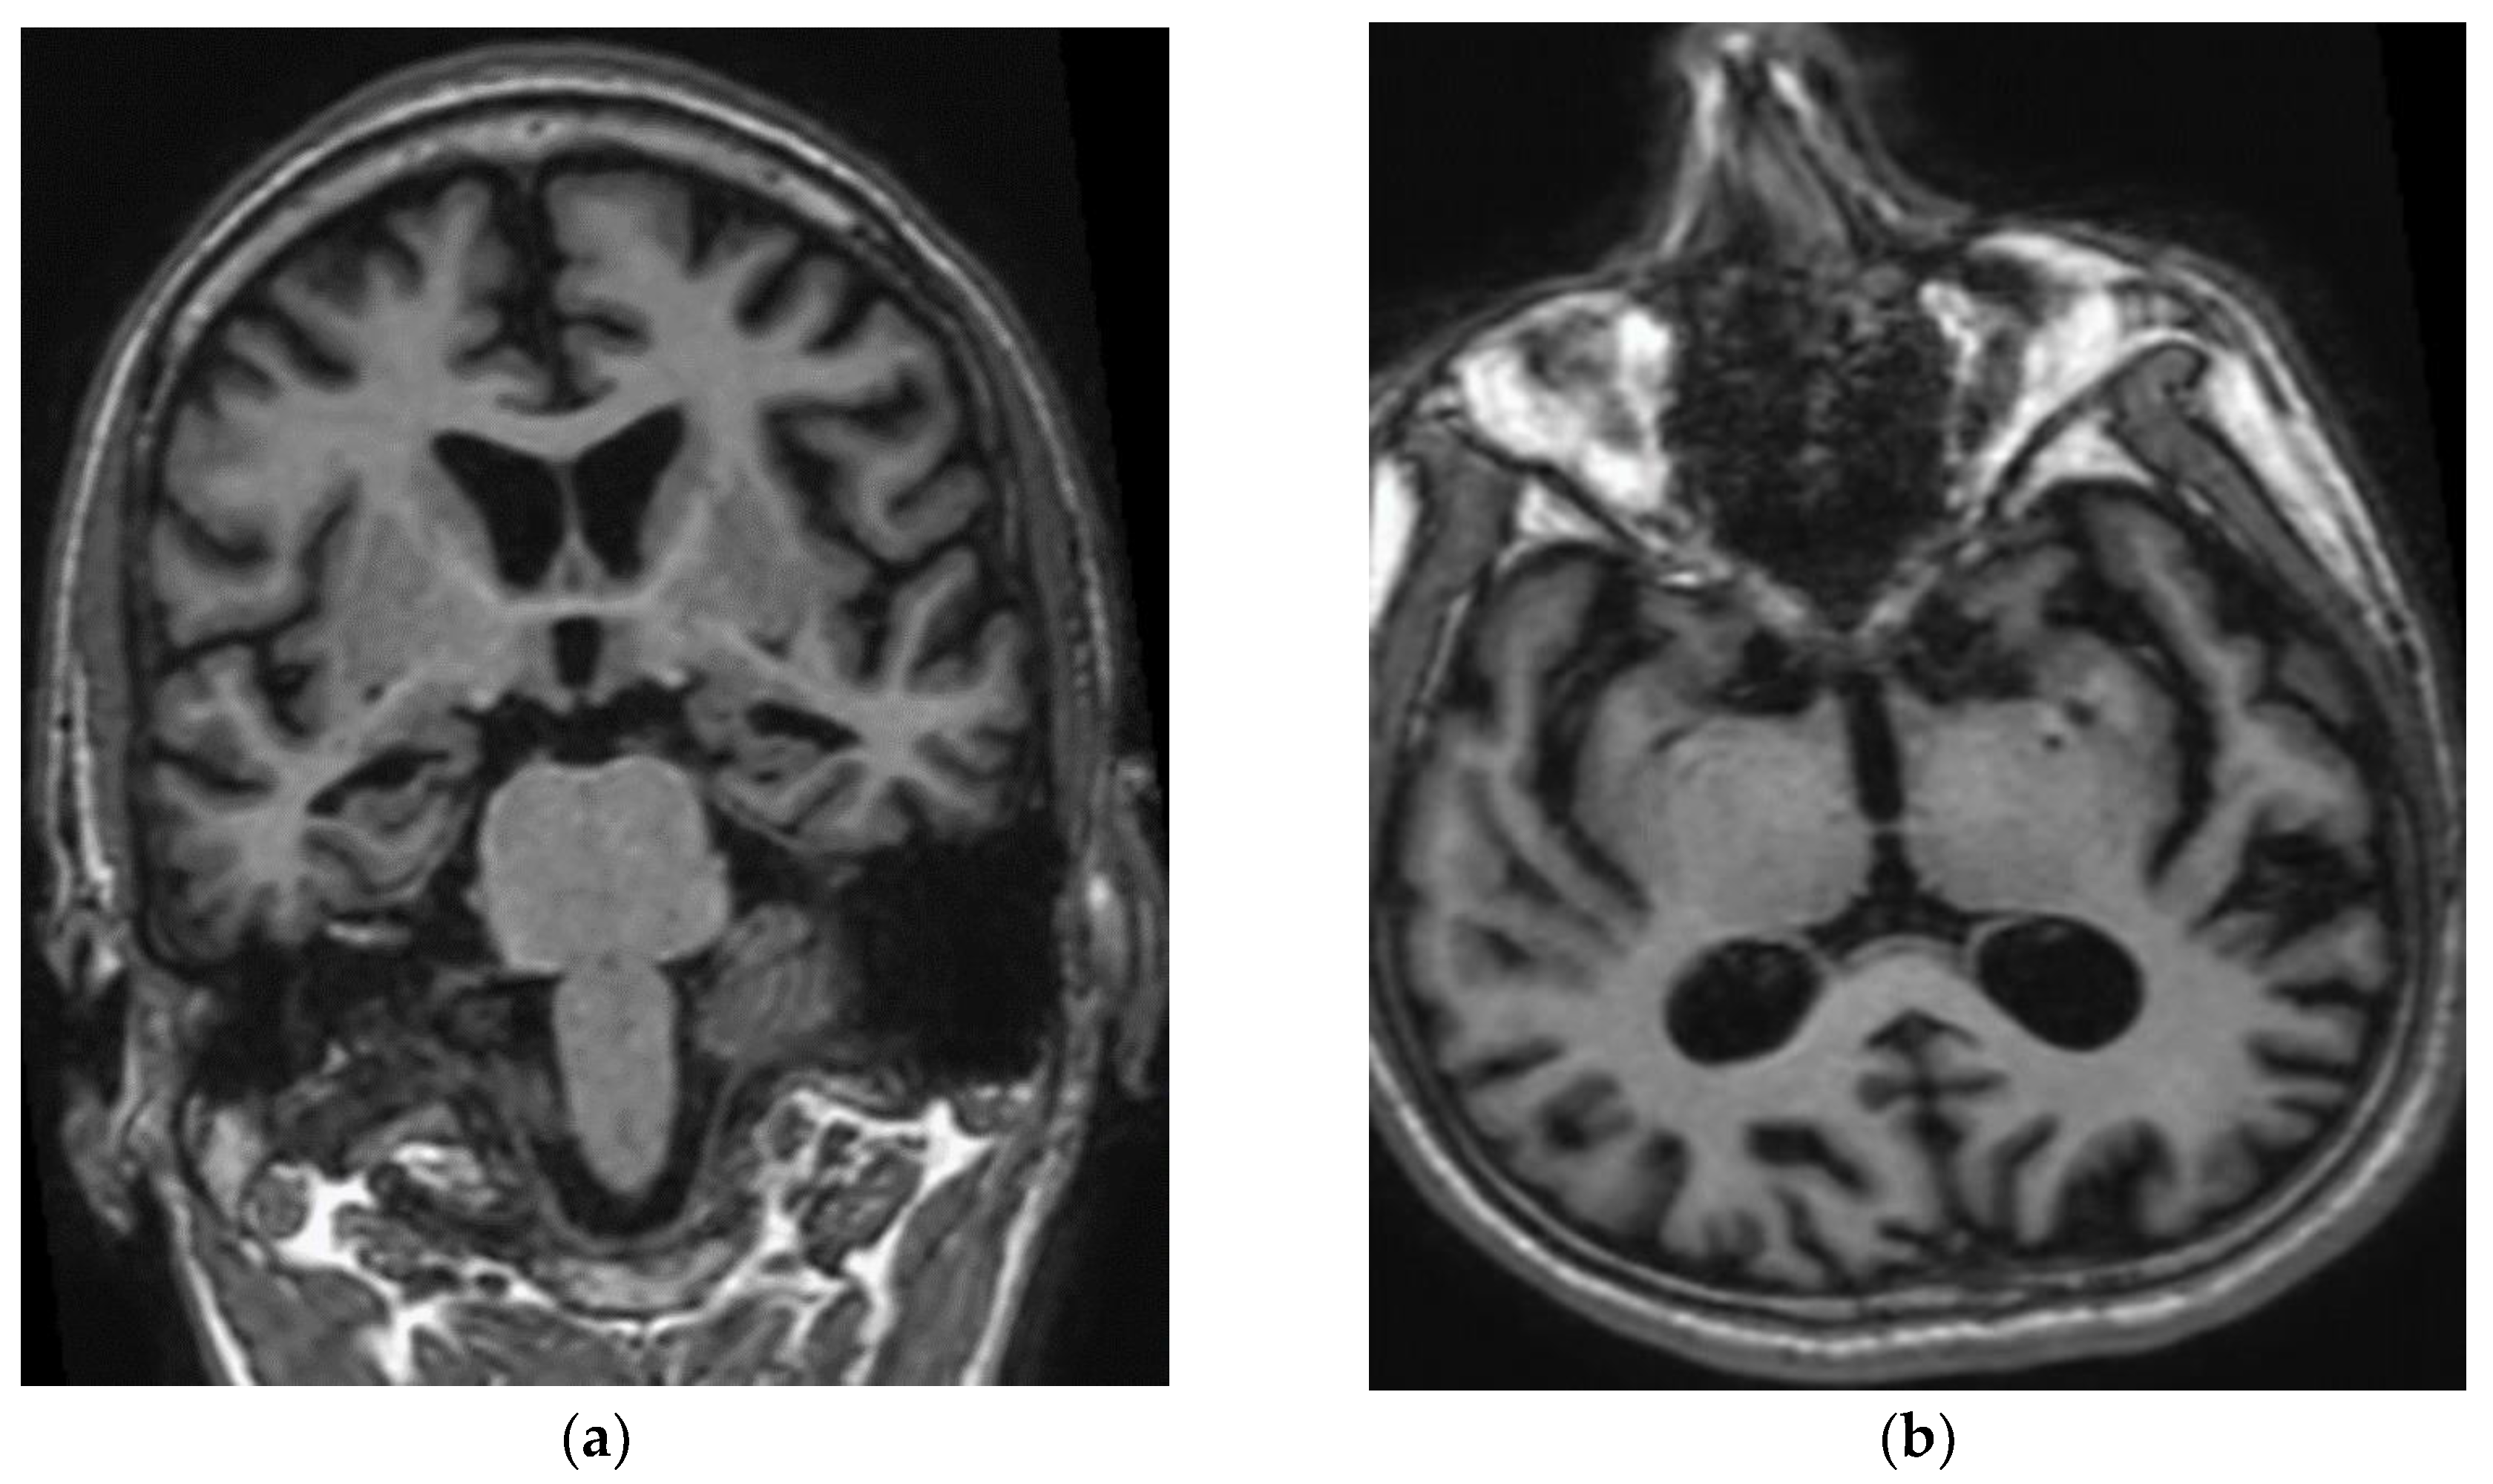

3.1. Subjects